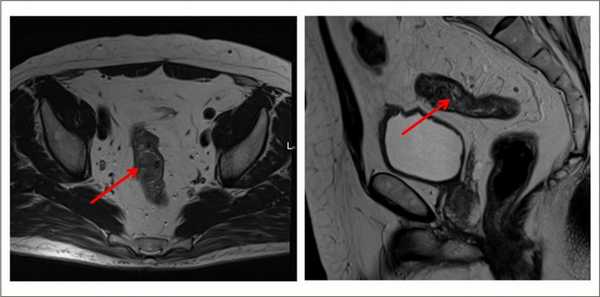

Для определения распространенности злокачественного процесса. Можно выполнять абдоминально – через брюшную стенку, и трансректально – через анальное отверстие.

Выявляет даже небольшие по размеру патологические очаги, метастазы и инвазию опухоли в соседние органы, ее топографическое положение относительно других структур. Метод безопасен, не создает радиационную нагрузку, в отличие от КТ.